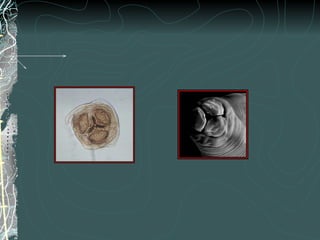

HUEVOS FECUNDADOS

Forma elíptica

Posee una cubierta protectora

gruesa:

Interna: membrana vitelina

Media: gruesa y transparente

Externa: albuminoidea

mamelonada de color café

HUEVOS NO FECUNDADOS

Son más largos y no

presentan la

membrana vitelina

interna

Ascaris lumbricoides : huevos